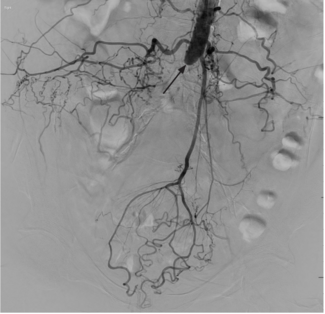

In the patient described herein, kissing-stent primary patency rate was improved via intravascular lithotripsy prior to stenting in highly calcified abdominal aortoiliac occlusions.

This case demonstrates the need for caution when using a collagen-based closure device as bailout for failure of suture-based devices in large-diameter arterial access.